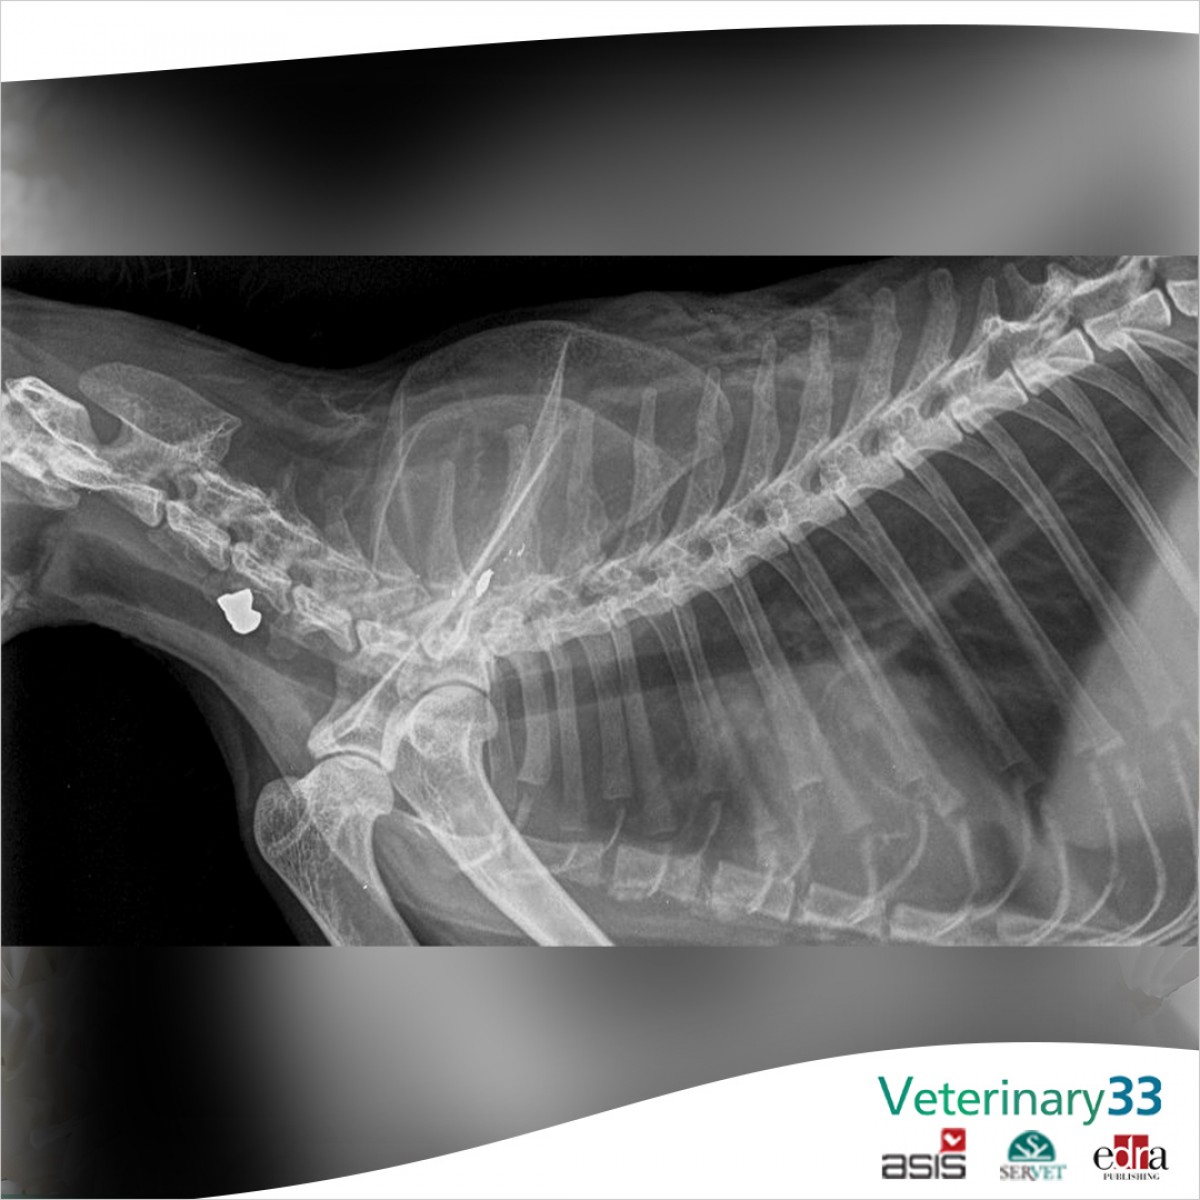

Outcomes and Complications Associated with Acute Gunshot Fractures in Cats and Dogs

Study design: Review of cats and dogs with radiographically confirmed acute gunshot fractures, presenting data on signalment, fracture location, fracture management (surgical vs. non-surgical, type of surgical repair), fracture comminution, extent of soft tissue trauma, postoperative complication, and overall outcome. A poor outcome was defined as patient death, major postoperative complication, or limb amputation (both as primary treatment and secondary to postoperative complications).

Results: Ninety-seven animals with 137 acute gunshot-induced fractures were identified. There were 21 (15.3%) maxillofacial, 16 (11.7%) vertebral column, 8 (5.8%) rib, 56 (40.9%) distal long bone (below stifle/cubital joint) and 36 (26.3%) proximal long bone (at or above stifle/cubital joint) fractures. Overall, 20/37 cases with sufficient follow-up details incurred a poor fracture outcome. Extensive soft tissue trauma at the fracture site was associated with an increased likelihood of poor outcome. The most common poor outcomes were primary limb amputations (7 cases) and postoperative complications (3 osteomyelitis/surgical site infections, 4 delayed/non-unions).

Conclusions: Gunshot fractures overall have high likelihood of poor outcome. Severe soft tissue injury is associated with complications. Mitigating poor outcome likely requires early aggressive wound management.